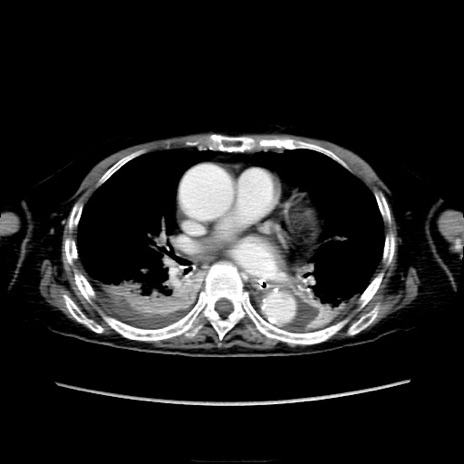

症例40(横断像)

【症例】90歳代女性

【主訴】腹痛・嘔吐

【現病歴】 食欲低下、嘔吐があり昨日他院受診。肺炎と診断され入院となる。入院後より腹部全体に圧痛あり。胃管留置され経過みていたが、症状持続するため、

当院転院となる。

【既往歴】胸椎圧迫骨折、胆石症

【身体所見】腹部:中央に激痛あり、圧痛あり、反跳痛不明

【データ】WBC 17100、CRP 18.82

横断像